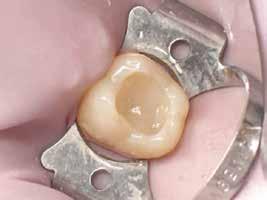

A gyökértömés elkészítése során meleg vertikális kompakciós technikát alkalmaztunk, sealerként pedig CeraSeal-t (Meta Biomed; 3. ábra) használtunk. A reszorbciós üreget Biodentine-nel (Septodont; 4. a–b ábra) töltöttük fel. A reszorbcióval érintett területtől koronális irányba elhelyezkedő csatornaszakaszt pedig tisztán meleg guttaperchával kezeltük. Ezt követően a lebenyszéleket visszafektettük, és varratok behelyezésével eredeti pozíciójuknak megfelelően rögzítettük. A koronai részt kompozit tömőanyag segítségével állítottuk helyre. Kontrollvizsgálatra 5, illetve 30 hónappal később került sor (5. ábra). A csontos telődés jelei már 5 hónap után észlelhetők voltak (6. a–c ábra). A 30 hónappal később végzett kontroll során sem találtunk csontban lévő lézióra, törésre vagy egyéb pathológiás elváltozásra utaló jeleket (7. a–b ábra)

MTA-val (Mineral Trioxide Aggregate; Harvard Dental) töltöttük fel. A léziótól koronális irányban elhelyezkedő gyökércsatorna-szakaszt meleg guttaperchával zártuk, majd az MTA-val kitöltött üregre egy kis darab kollagénszivacsot helyeztünk és a lebenyt varratok segítségével eredeti pozíciójában rögzítettük (12. a–b; 13. a–b. ábra). A fog koronai részét Gradia kompozit tömőanyaggal állítottuk helyre (GC; 14. a–b; 15. ábra). Kontrollvizsgálatra két (16. a–b ábra) és négy évvel (17. a–b ábra) később került sor. A kontrollfelvételeken a bukkális kortikális jelenléte volt észlelhető. A fog körüli parodoncium egészséges volt, valamint a páciens sem számolt be tünetekről.